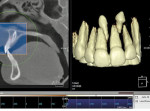

Finally, whether clinicians purchase or simply use the data from CBCT machines in their practice, it is important—perhaps imperative—that they obtain training beyond the manufacturer’s hands-on, in-office introduction. Until trained, a dentist or dental specialist is simply not used to seeing a patient image in the axial plane of section. These types of images, as well as the images in the coronal and sagittal planes and the anatomic data within them, must be mastered before a clinician can feel comfortable using CBCT (Figure 1, Figure 2, and Figure 3).